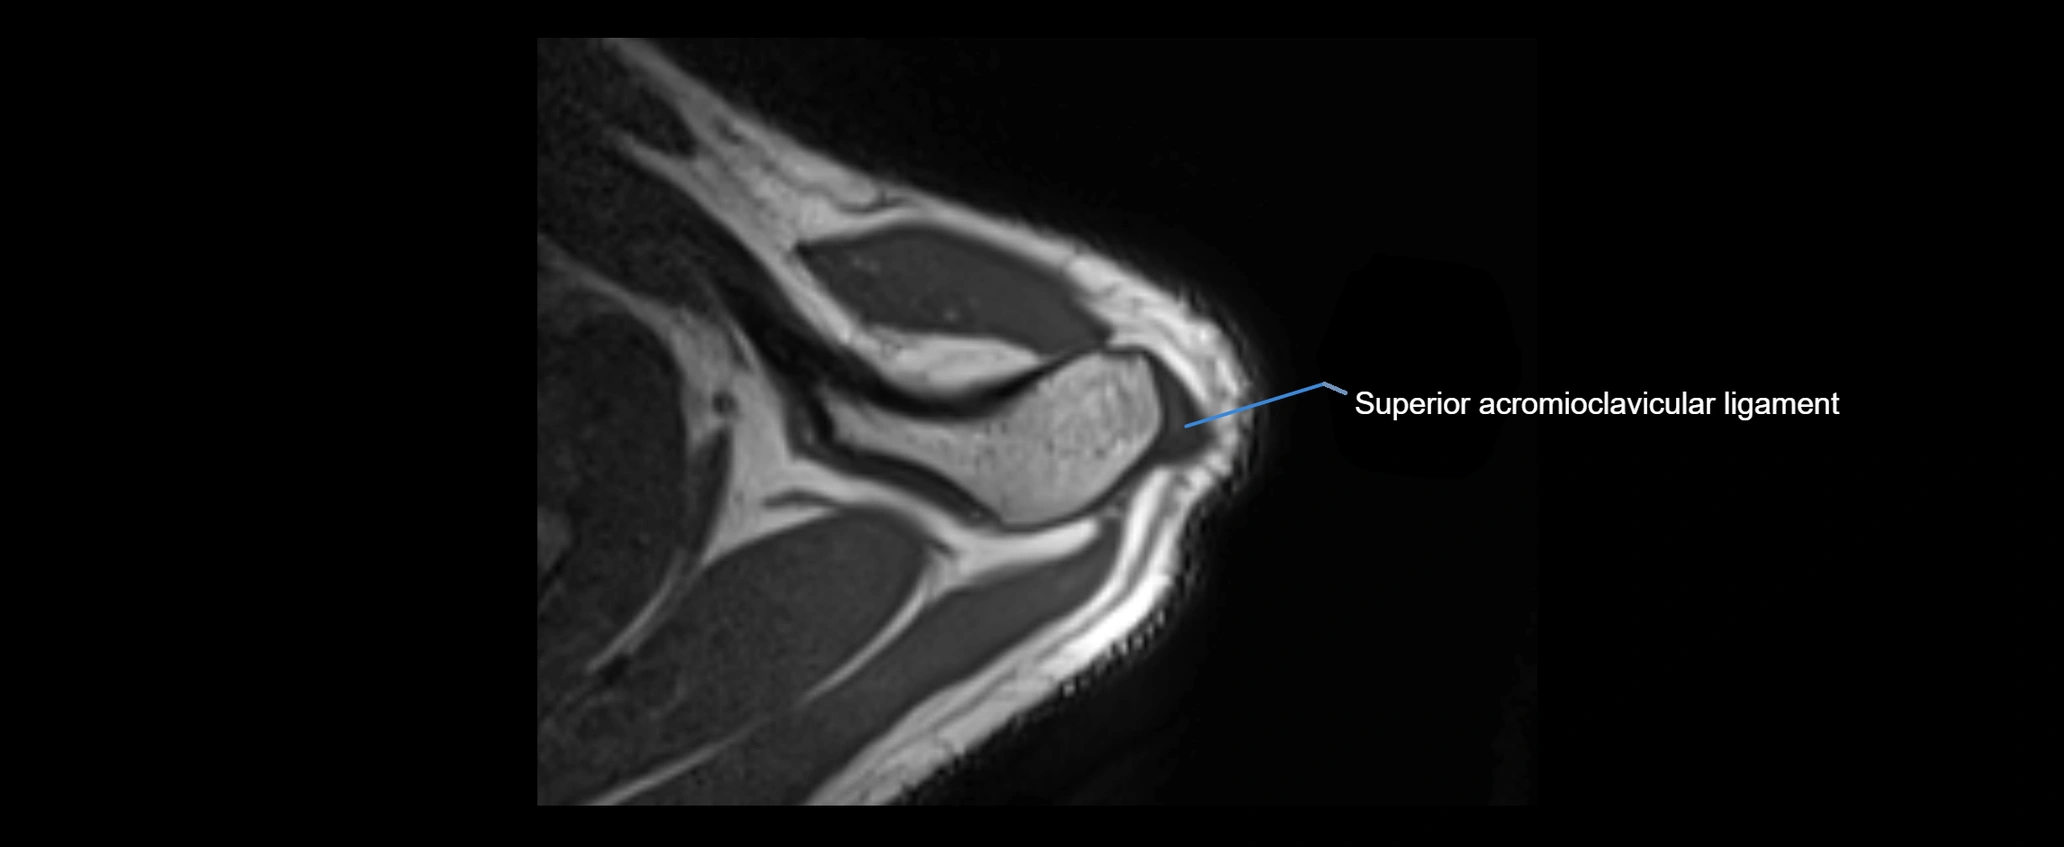

MRI images

image

MRI Appearance

• T1-weighted images:

• Normal ligament: Low signal (dark linear band) spanning acromion to clavicle.

• Surrounding fat planes: Bright, delineating the ligament clearly.

• Tears: Discontinuity or irregular thickening with intermediate-to-bright signal.

• Chronic injury: Thinning, fraying, or irregular low-signal fibers with adjacent scarring.

• T2-weighted images:

• Normal ligament: Low signal, homogeneous.

• Partial tear or sprain: Focal hyperintensity or thickening.

• Complete tear: Discontinuity with fluid-bright gap between clavicle and acromion.